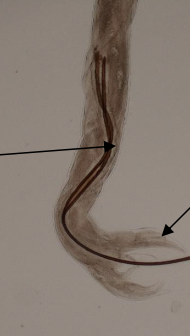

Which morphological features shown in this picture help identify the sex of Nematodirus?

Male

Long thin spicules and extend well beyond the worm

Presence of bursa at the tail end